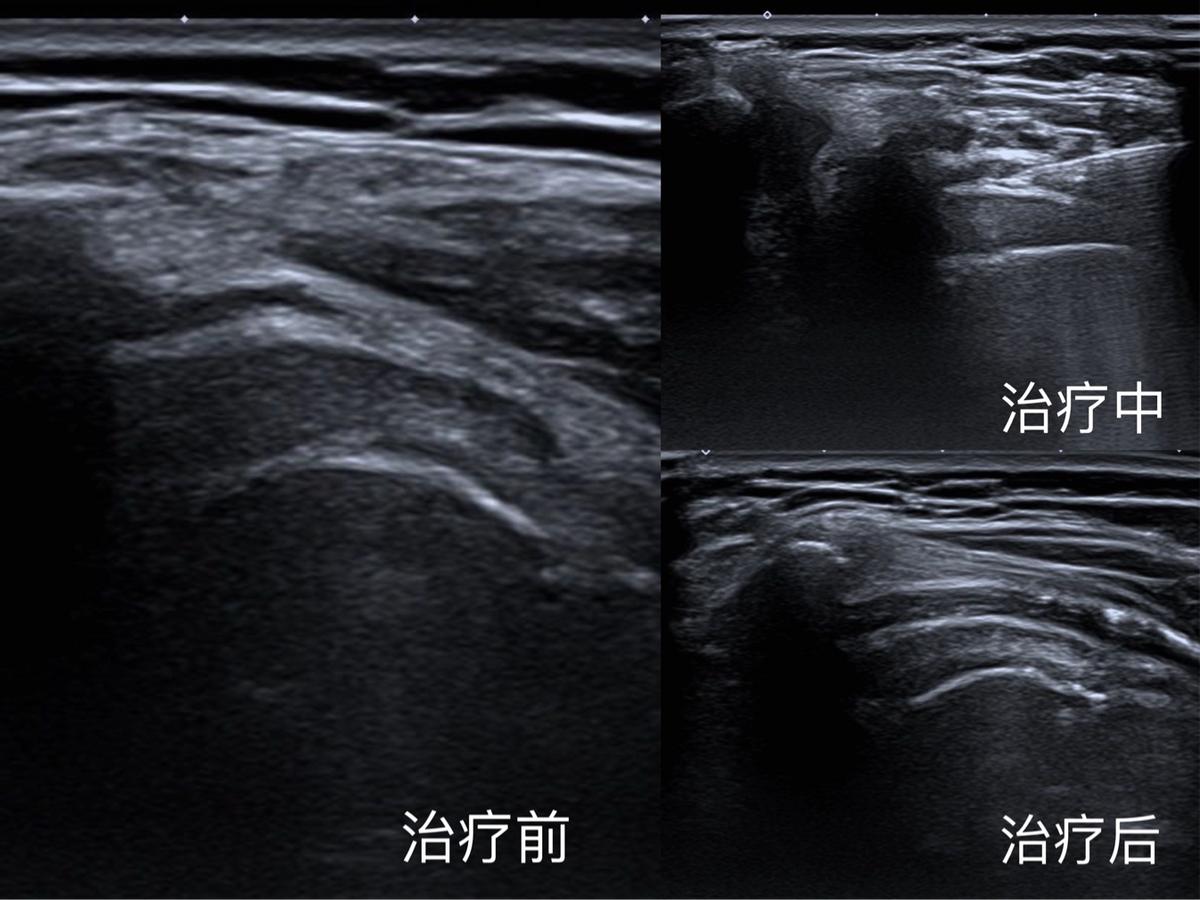

谢某,女,50岁,因肩周炎导致疼痛及肩关节活动明显受限,严重影响工作及生活,来我院骨科求助,骨科医生建议通过肩关节腔内药物注射治疗来缓解疼痛,考虑到盲穿治疗可能出现的并发症,建议患者行超声引导下介入治疗,于是来到我院群力超声医学科,姜岩医生为对其肩关节进行了详细的检查,细致为患者讲解超声可视环境下肩关节重要解剖结构及病变部位,并顺利完成超声引导下肩关节腔内药物注射及松解治疗。

治疗后患者症状明显减轻,立竿见影,困扰她多年的病痛终于解决了!